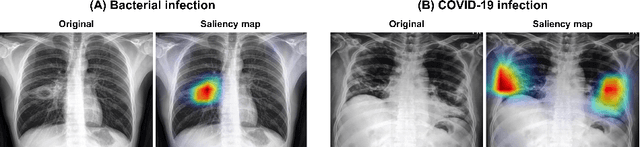

Abstract:Under the global pandemic of COVID-19, building an automated framework that quantifies the severity of COVID-19 and localizes the relevant lesion on chest X-ray images has become increasingly important. Although pixel-level lesion severity labels, e.g. lesion segmentation, can be the most excellent target to build a robust model, collecting enough data with such labels is difficult due to time and labor-intensive annotation tasks. Instead, array-based severity labeling that assigns integer scores on six subdivisions of lungs can be an alternative choice enabling the quick labeling. Several groups proposed deep learning algorithms that quantify the severity of COVID-19 using the array-based COVID-19 labels and localize the lesions with explainability maps. To further improve the accuracy and interpretability, here we propose a novel Vision Transformer tailored for both quantification of the severity and clinically applicable localization of the COVID-19 related lesions. Our model is trained in a weakly-supervised manner to generate the full probability maps from weak array-based labels. Furthermore, a novel progressive self-training method enables us to build a model with a small labeled dataset. The quantitative and qualitative analysis on the external testset demonstrates that our method shows comparable performance with radiologists for both tasks with stability in a real-world application.